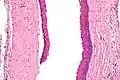

Odontogenic keratocysts have a diagnostic histological appearance. Under the microscope, OKCs vaguely resemble keratinized squamous epithelium;[14] however, they lack rete ridges and often have an artifactual separation from their basement membrane.[2]

The fibrous wall of the cyst is usually thin and uninflamed. The epithelial lining is thin with even thickness and parakeratinised with columnar cells in the basal layer which have focal reverse polarisation (nuclei are on the opposite pole of the cell).[12] The basal cells are an indication of the odontogenic origin as they resemble pre-ameloblasts. The epithelium can separate from the wall, resulting in islands of epithelium. These can go on to form 'satellite' or 'daughter' cysts, leading to an overall multilocular cyst.[9] Presence of daughter cysts is particularly seen in those with NBCCS.[12] Inflamed cysts show hyperplastic epithelium which is no longer characteristic of OKCs and can have resemblance to radicular cysts instead. Due to areas of focal inflammation, a larger biopsy is required for correct diagnosis of odontogenic keratocysts.[9]